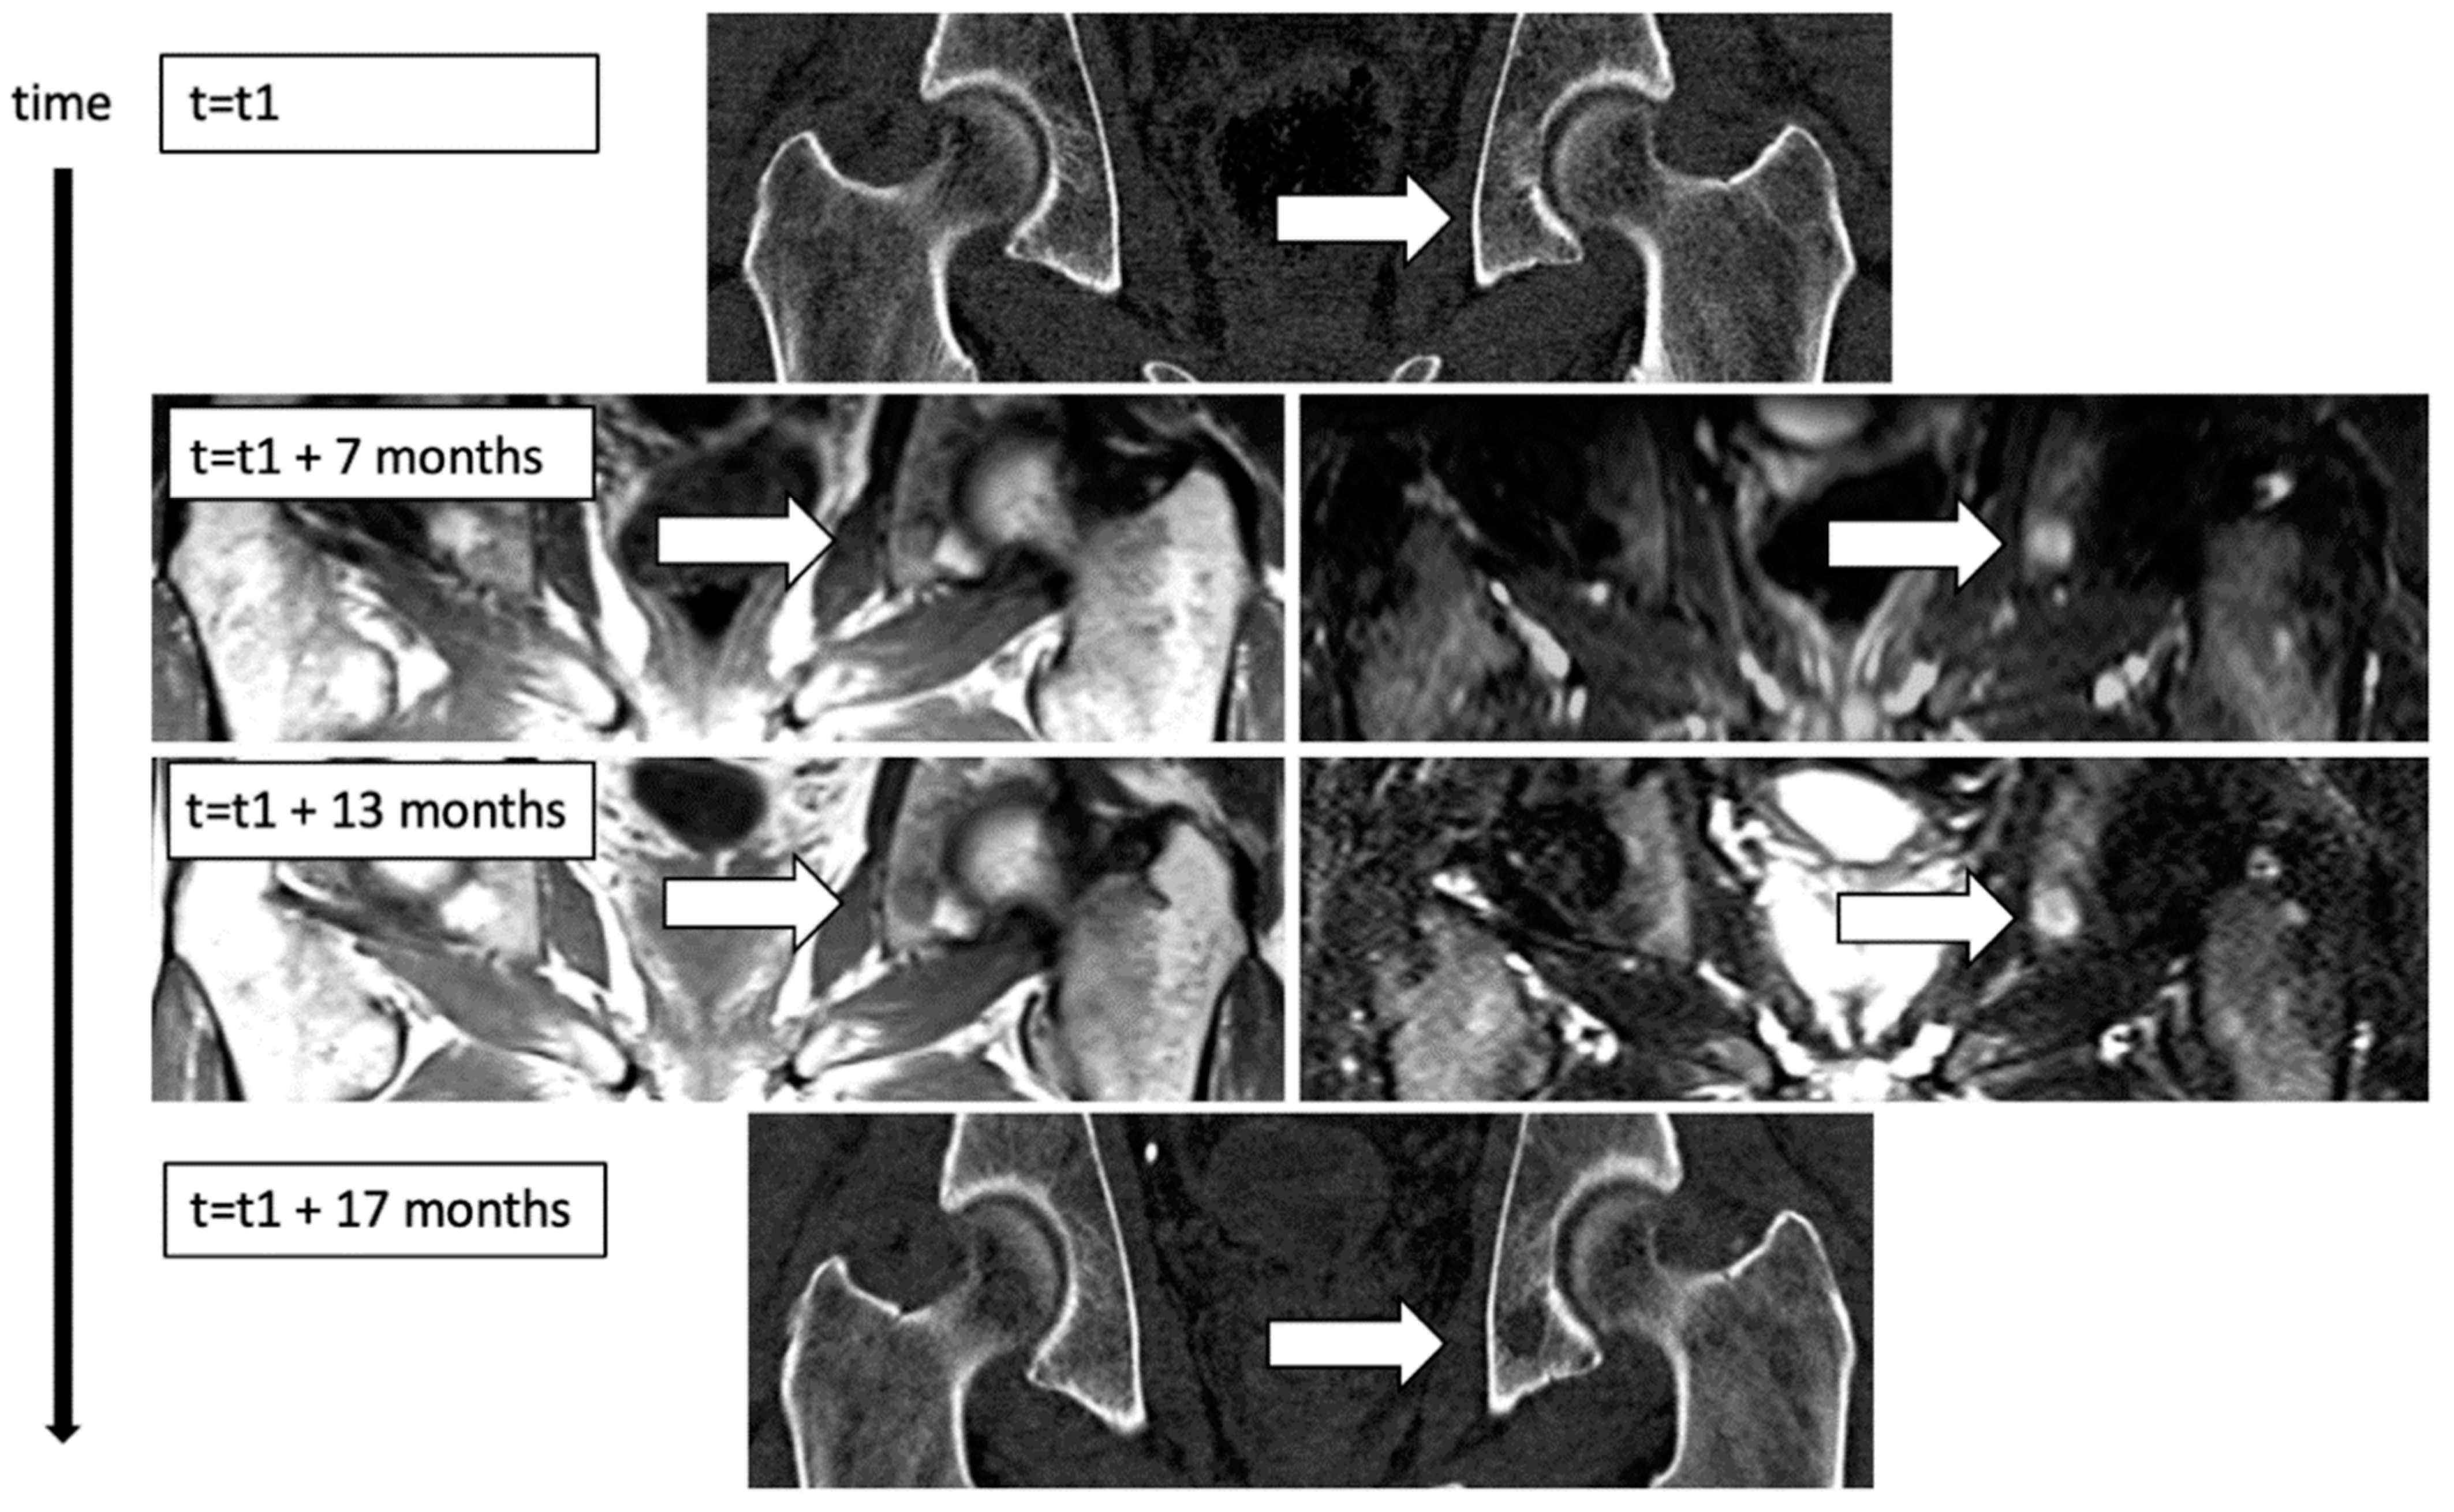

3.1. Spatial Heterogeneity in Local Growth Dynamics

4.1. Spatial Heterogeneity in Growth Dynamics between Different Focal Lesions